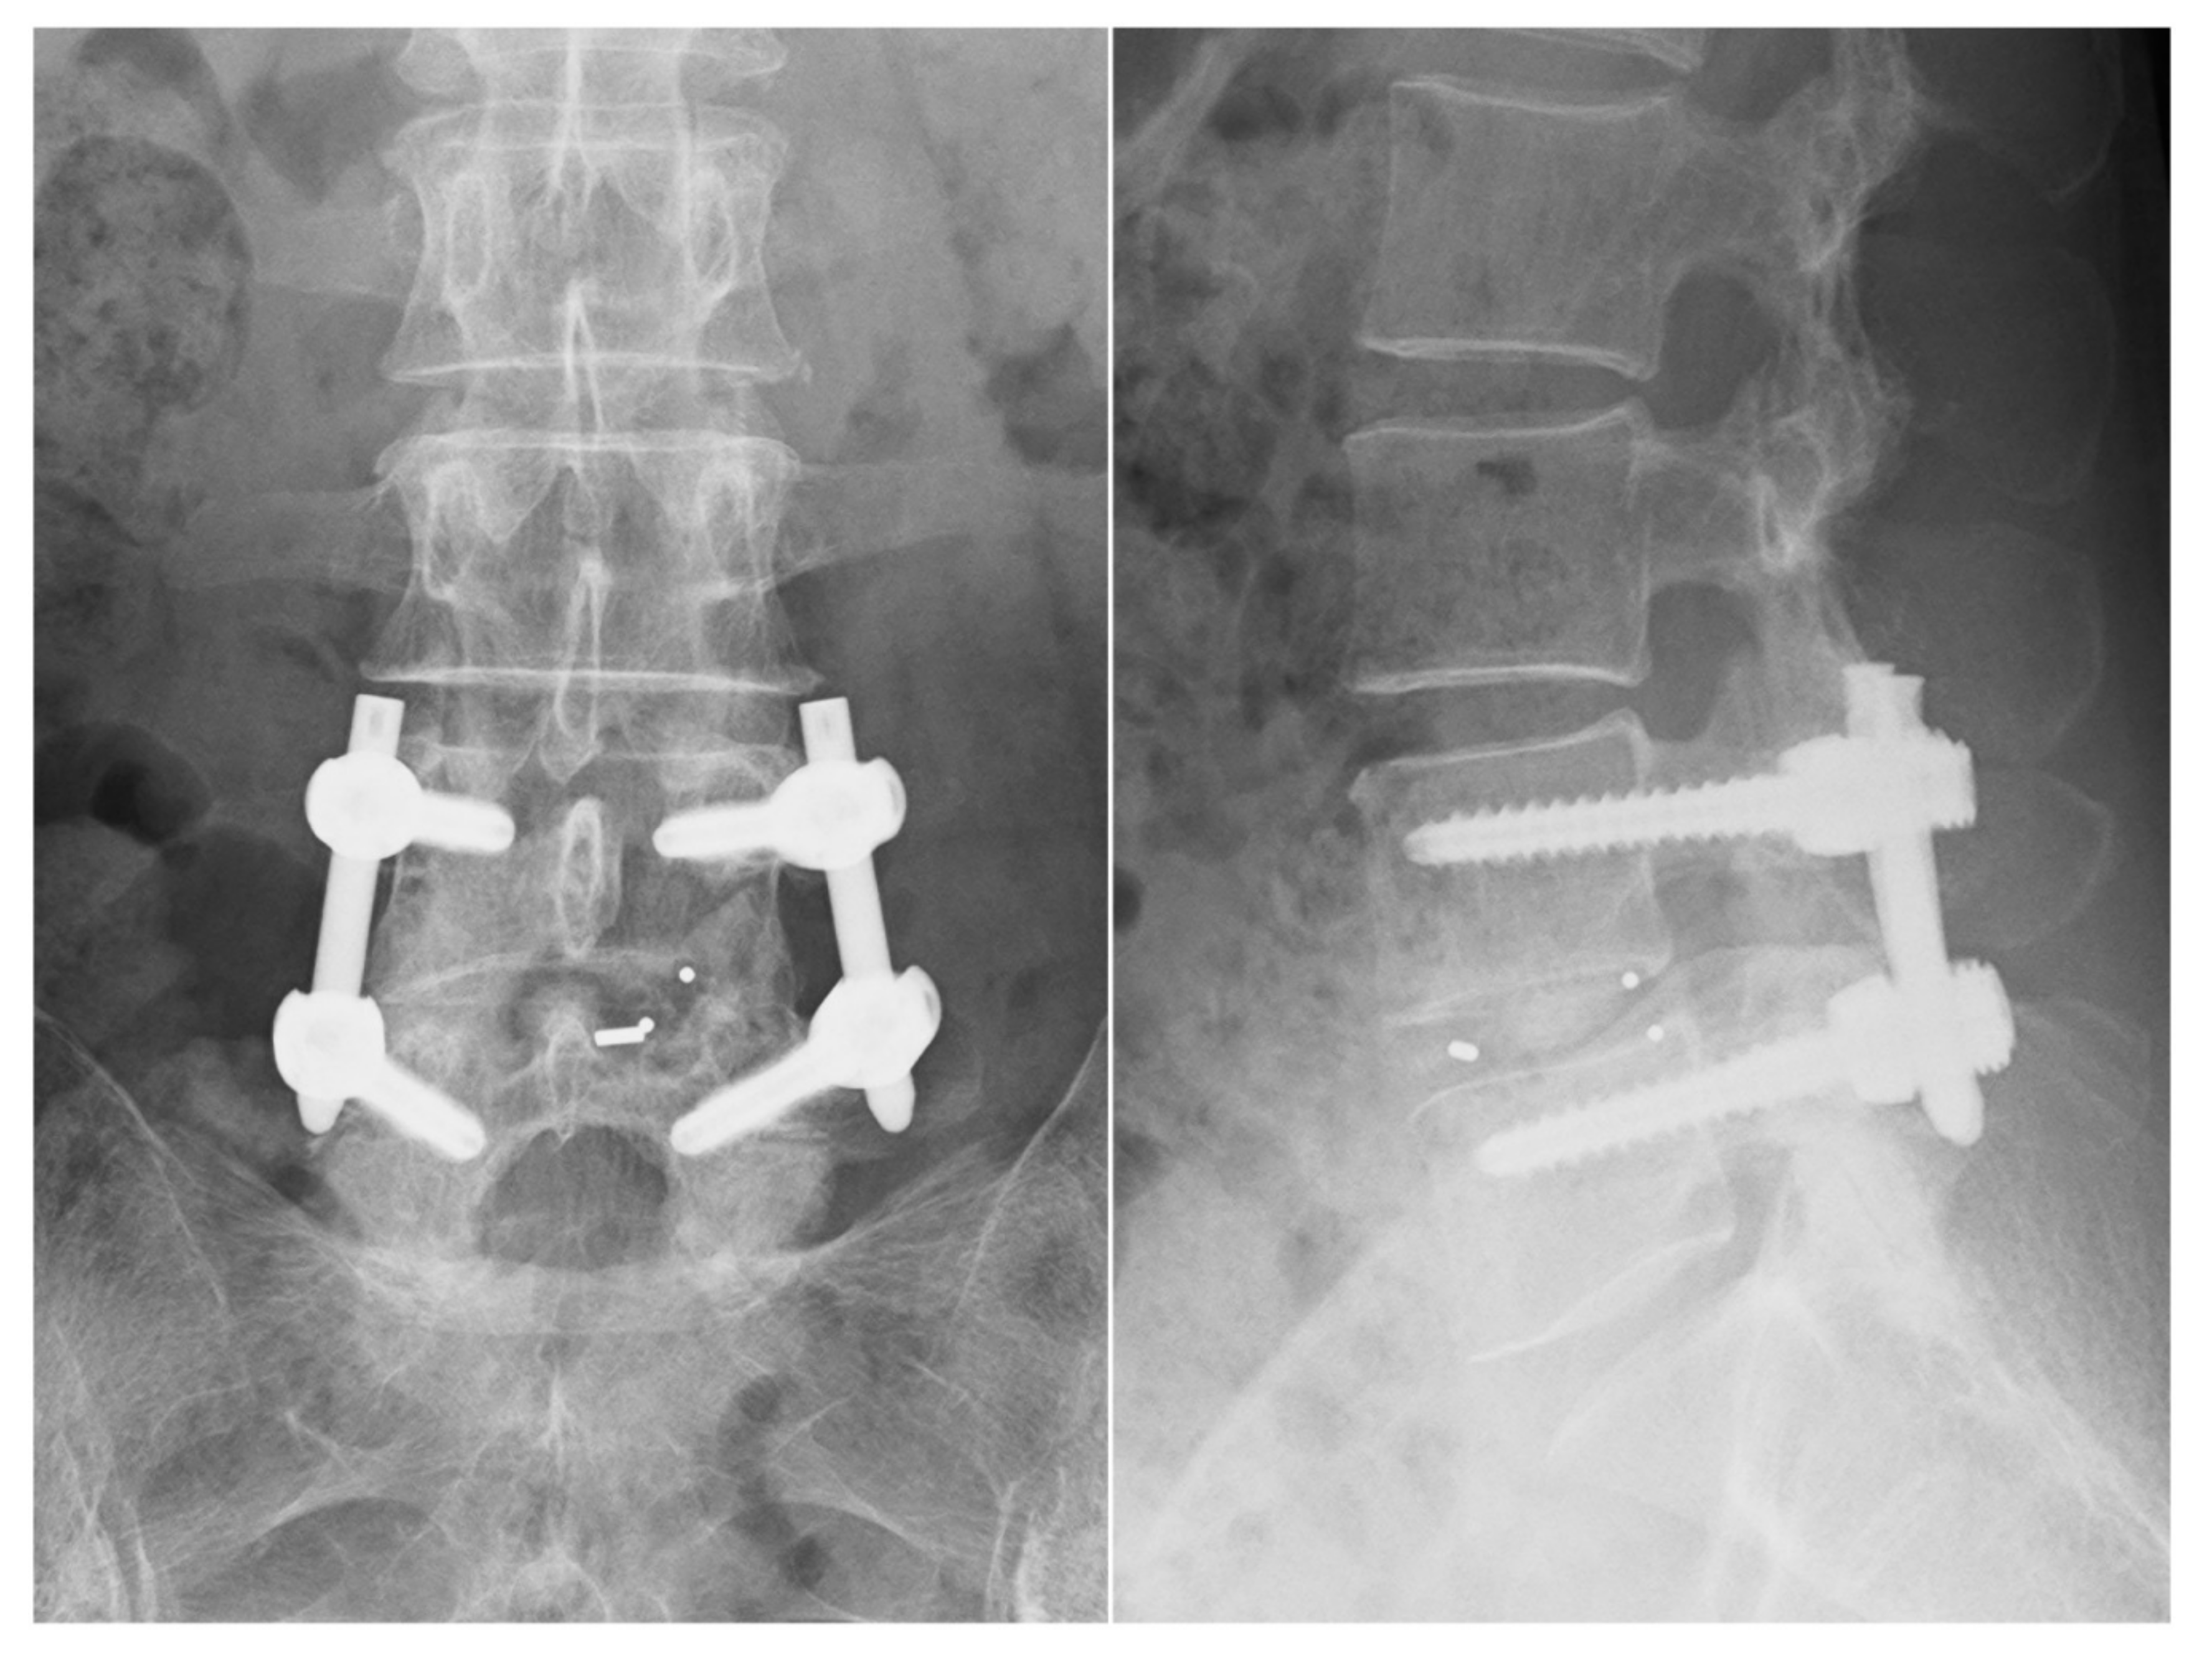

Posterior Oblique Square Decompression with a Three-Step Wanding Technique in Tubular Minimally Invasive Transforaminal Lumbar Interbody Fusion: Technical Report and Mid-Long-Term Clinical Outcomes

2.2. Surgical Procedures